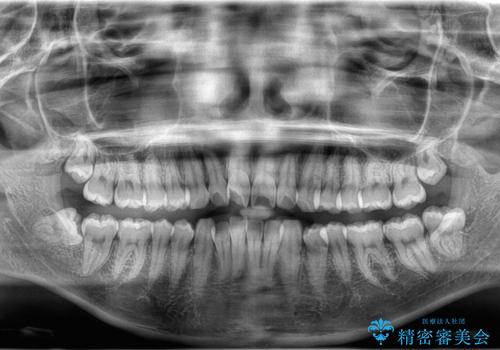

- 「歯のでこぼこと捻じれを治したい」を主訴に来院された患者様です。矯正検査の結果、上顎前歯がかなり唇側傾斜という結果になったので上下左右4番を抜歯をしワイヤー矯正で治療を行いました。

抜歯矯正でしたが順調に治療が進み2年で矯正治療を終えることが出来ました。歯のでこぼこや捻じれが治り、口元も下がって患者さんも大変満足されていました。